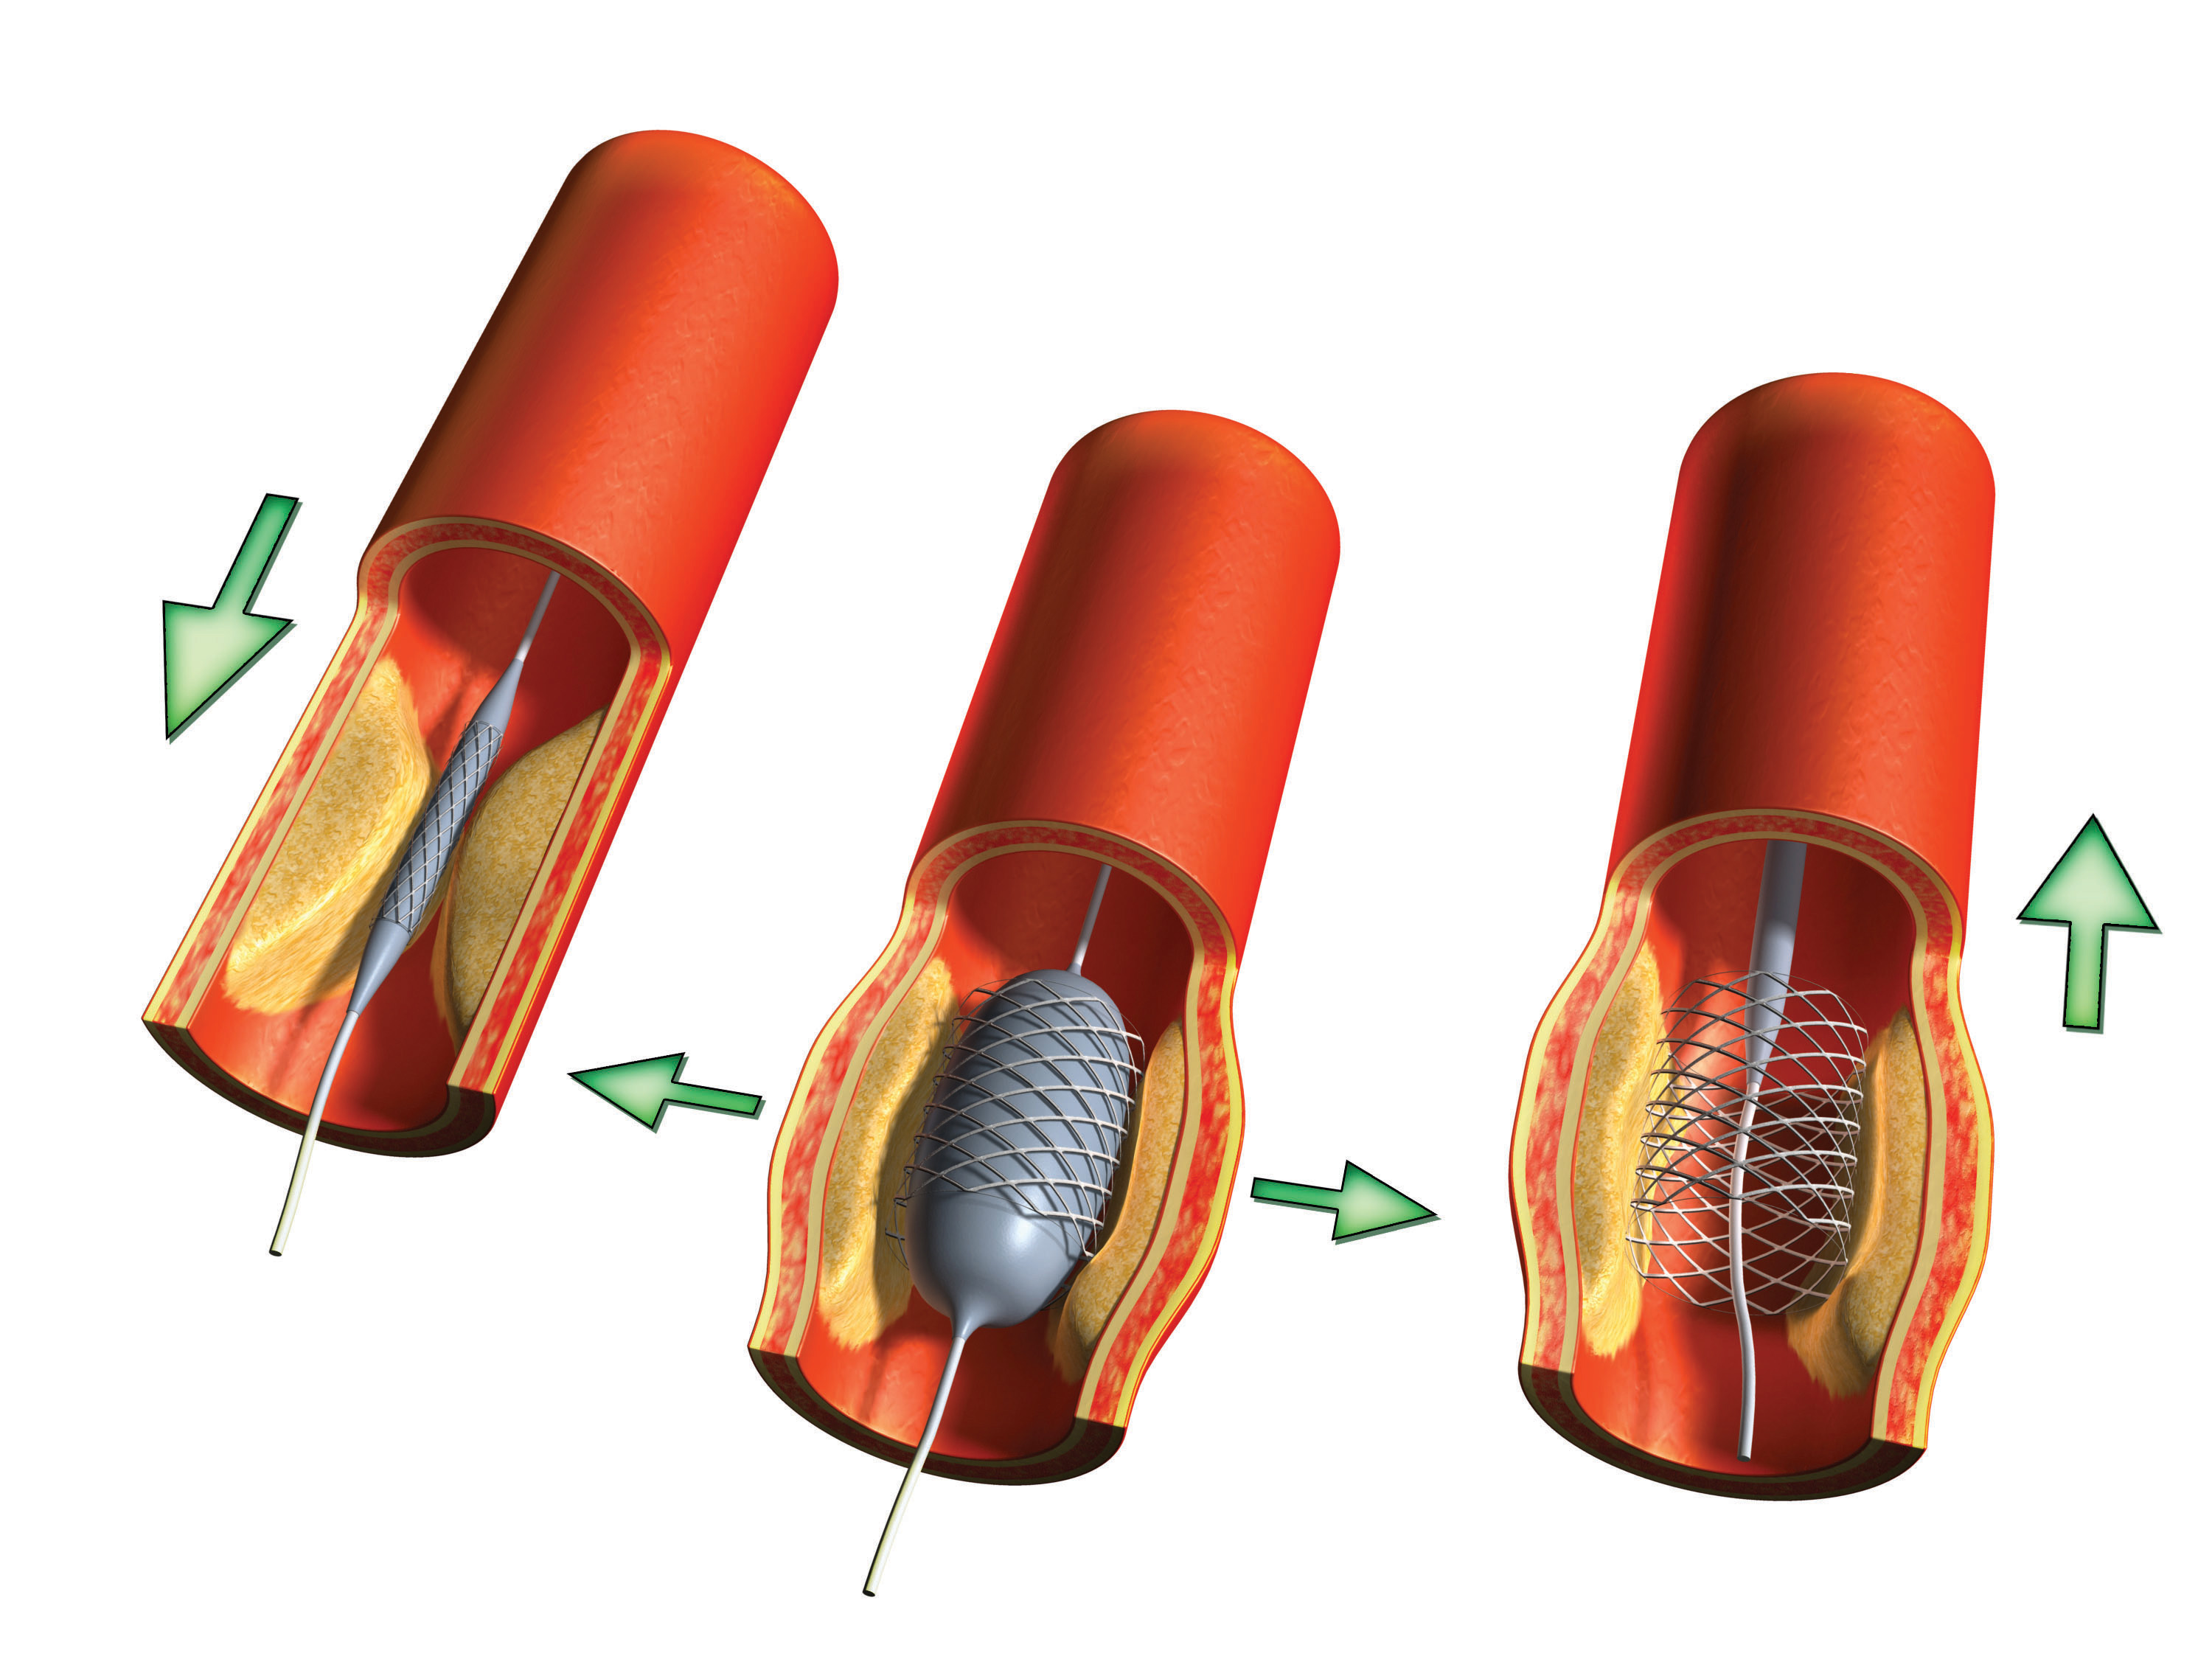

Изображения, связанные с атеросклерозом нижних конечностей и его лечением